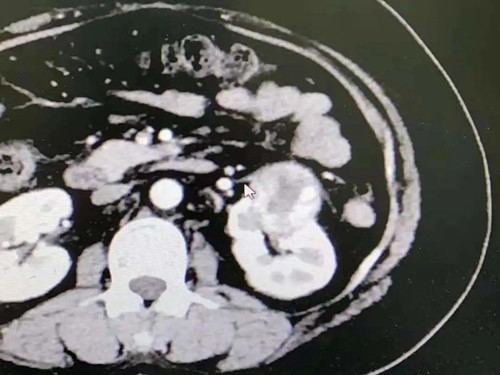

泌尿外科副主任刘荣新详细为患者查体,并根据社区医生的病情描述及查体结果,当天便为患者开具了具有针对性的肾脏增强CT检查。结果明确患者肾脏区域有肿瘤生长,约4㎝大,提示:左肾透明细胞癌可能。

患者办理入院并快速完善相关检查后,发现其血糖高达17mmol/l,明确为2型糖尿病,经医院多学科联合会诊给予胰岛素降糖治疗。三日后患者血糖平稳,术前准备完善后进行了腹腔镜肾癌根治术。全麻术中完整切除肿瘤及其周围脂肪囊,过程顺利,术后患者恢复良好,术后病理明确诊断为:左肾透明细胞癌,未见肾门淋巴结转移。